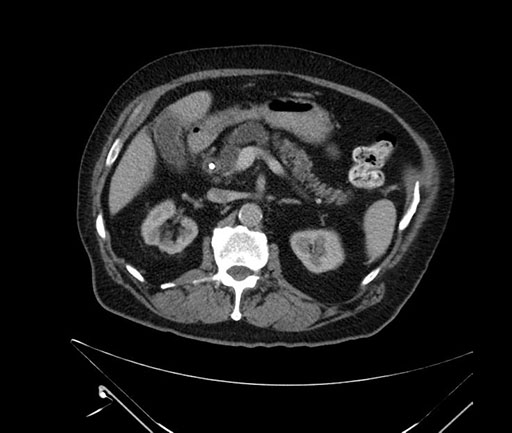

Imaging Analysis

Look through the patient's CT scan to identify any areas of concern for the necessary procedure.

Based on your CT findings, which issue(s) would give reason for "planned slowing down moment(s)" in this case?

Considering a standard Whipple procedure, what step(s) of the operation would you do differently in this case?